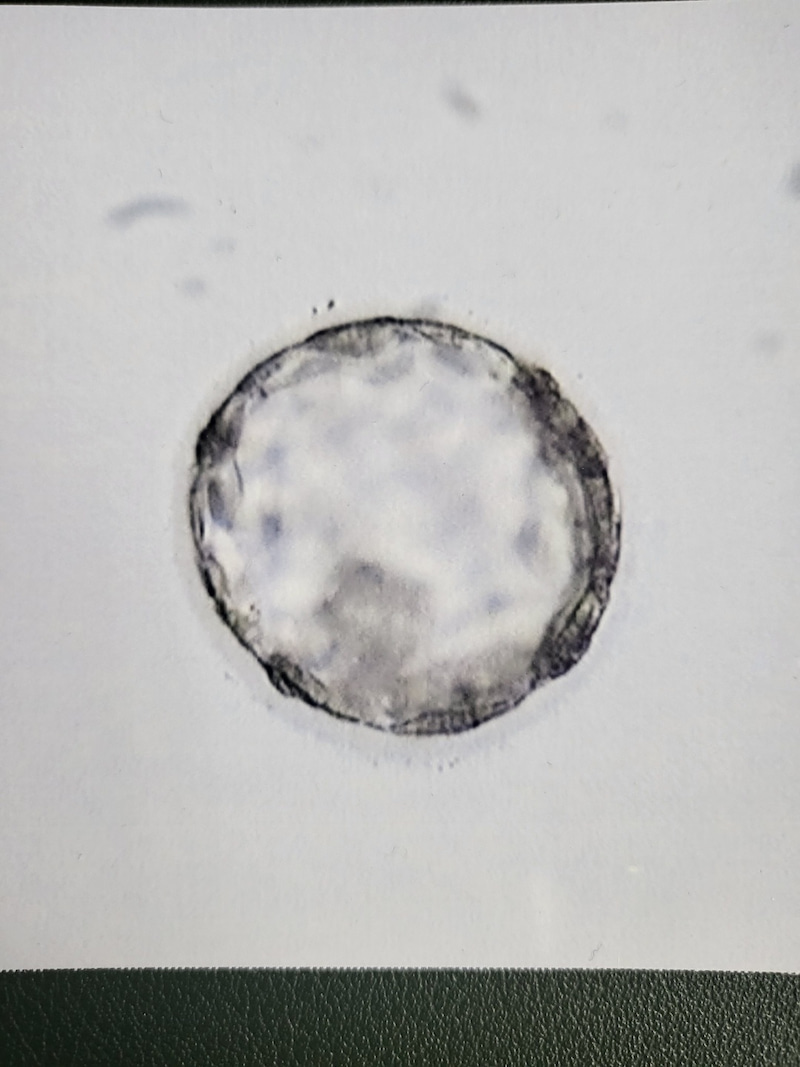

採卵当日に移植した胚の写真をもらったので添付させていただきます。

1つ目の胚盤胞のグレードと評価についてです。

こちらの胚盤胞は、拡張期胚盤胞4ΒΒだと思います。

推定でICM(将来、胎児になる細胞)はB評価、

TE(将来、胎盤になる細胞)はB評価だと思われます。

ICMにはピントが合っていないので、B評価は「おそらく」です。

フラグメントは15%はあるのかな、というところです。

(15%は少ない方です。)

ただ、別の写真のではまたフラグメントがもう少しあるように見えるかもしれませんね。

標準的な胚盤胞で良いですね。